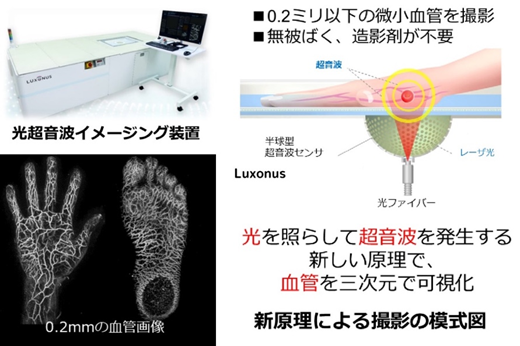

第4位 光超音波イメージング装置「LME-01」(Luxonus(ルクソナス))

株式会社Luxonusは、内閣府が主催する第6回日本医療研究開発大賞にて「スタートアップ奨励賞」を受賞し、活躍が期待されている。本製品は2022年にも同企画で取り上げているが、最大180mm×290mmの範囲を0.2ミリメートルの分解能で撮影し、手のひらであれば2分20秒ほどで3次元(3D)画像を得られる。血管の静止画だけではなく、血流の状態が分かる動画も撮影できる。また、がんの新生血管の評価やリンパ管の流れを画像化する研究も進められており、新たな画像評価のポテンシャルを有している。